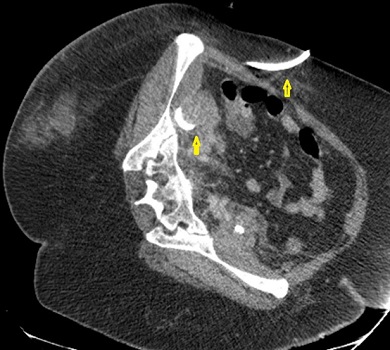

Παρακάτω φαίνονται οι παροχετεύσεις (κίτρινα βέλη) που καταλήγουν εντός των αποστηματικών κοιλοτήτων σε διάφορες τομές της αξονικής τομογραφίας.